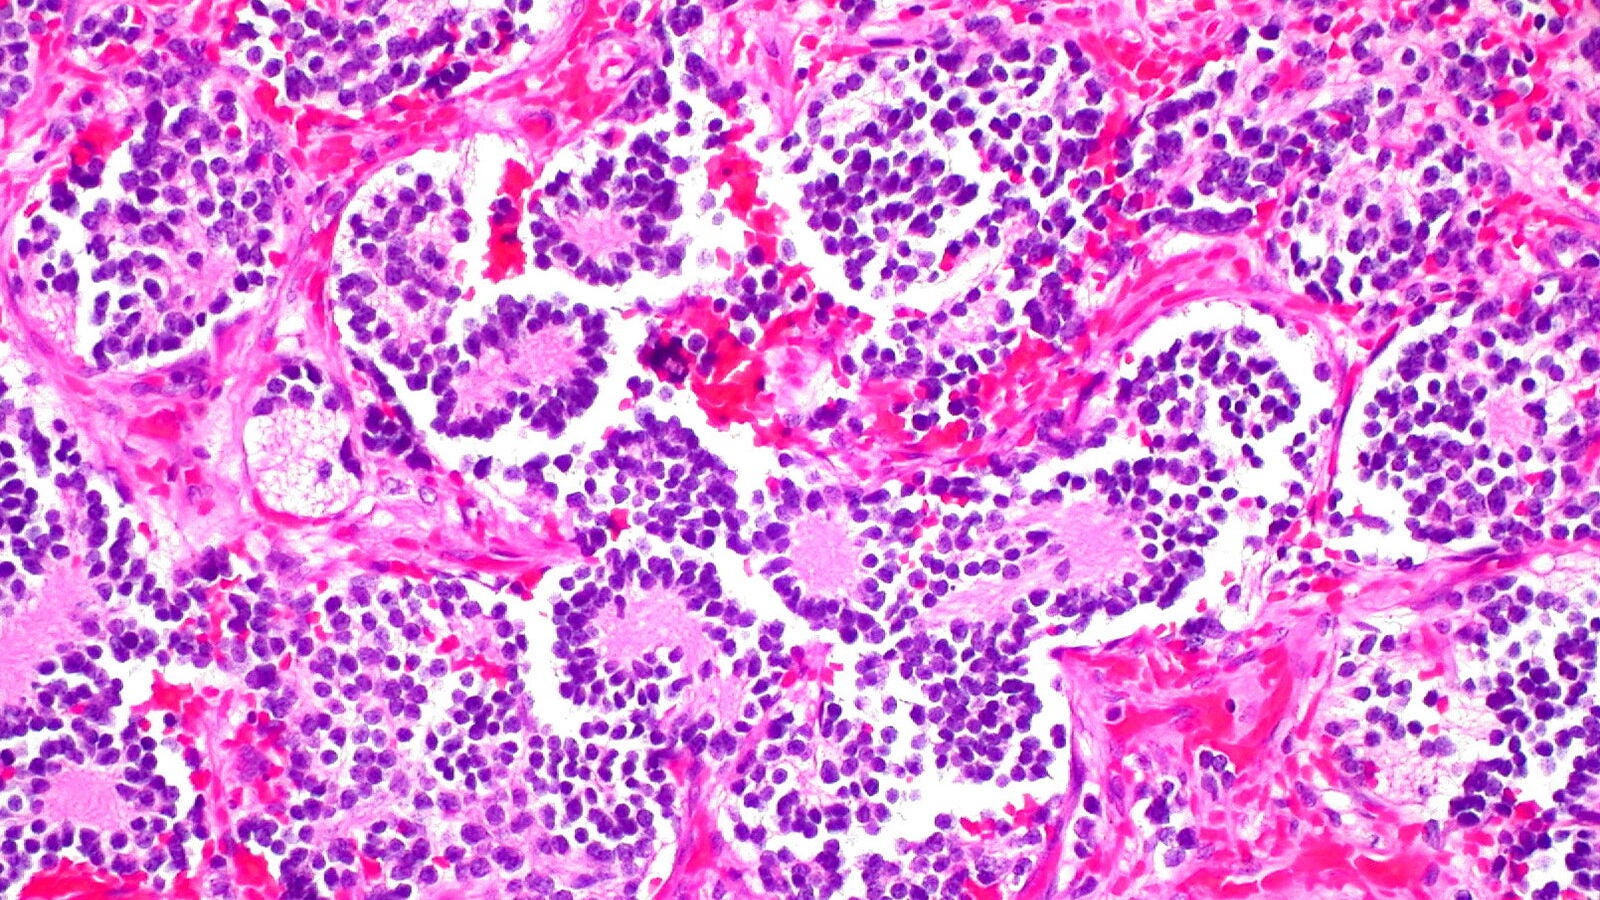

Y la clave está en que el neuroblastoma se caracteriza por un alto estrés oxidativo debido al metabolismo activo en las células cancerosas (básicamente su capacidad para reproducirse sin parar). Por lo tanto, los tumores dependen de enzimas antioxidantes como PRDX6 y GSTP1 para gestionar el estrés y evitar la muerte celular. Los niveles elevados de estas enzimas se asocian con un peor pronóstico.

"Al inhibir estas enzimas en cultivos celulares, así como en modelos murinos, algunas células tumorales mueren mientras que otras maduran y se convierten en neuronas sanas y activas, lo que dificulta el crecimiento tumoral", añade Judit Liaño-Pons, experta española en biología oncológica molecular y coautora del estudio.